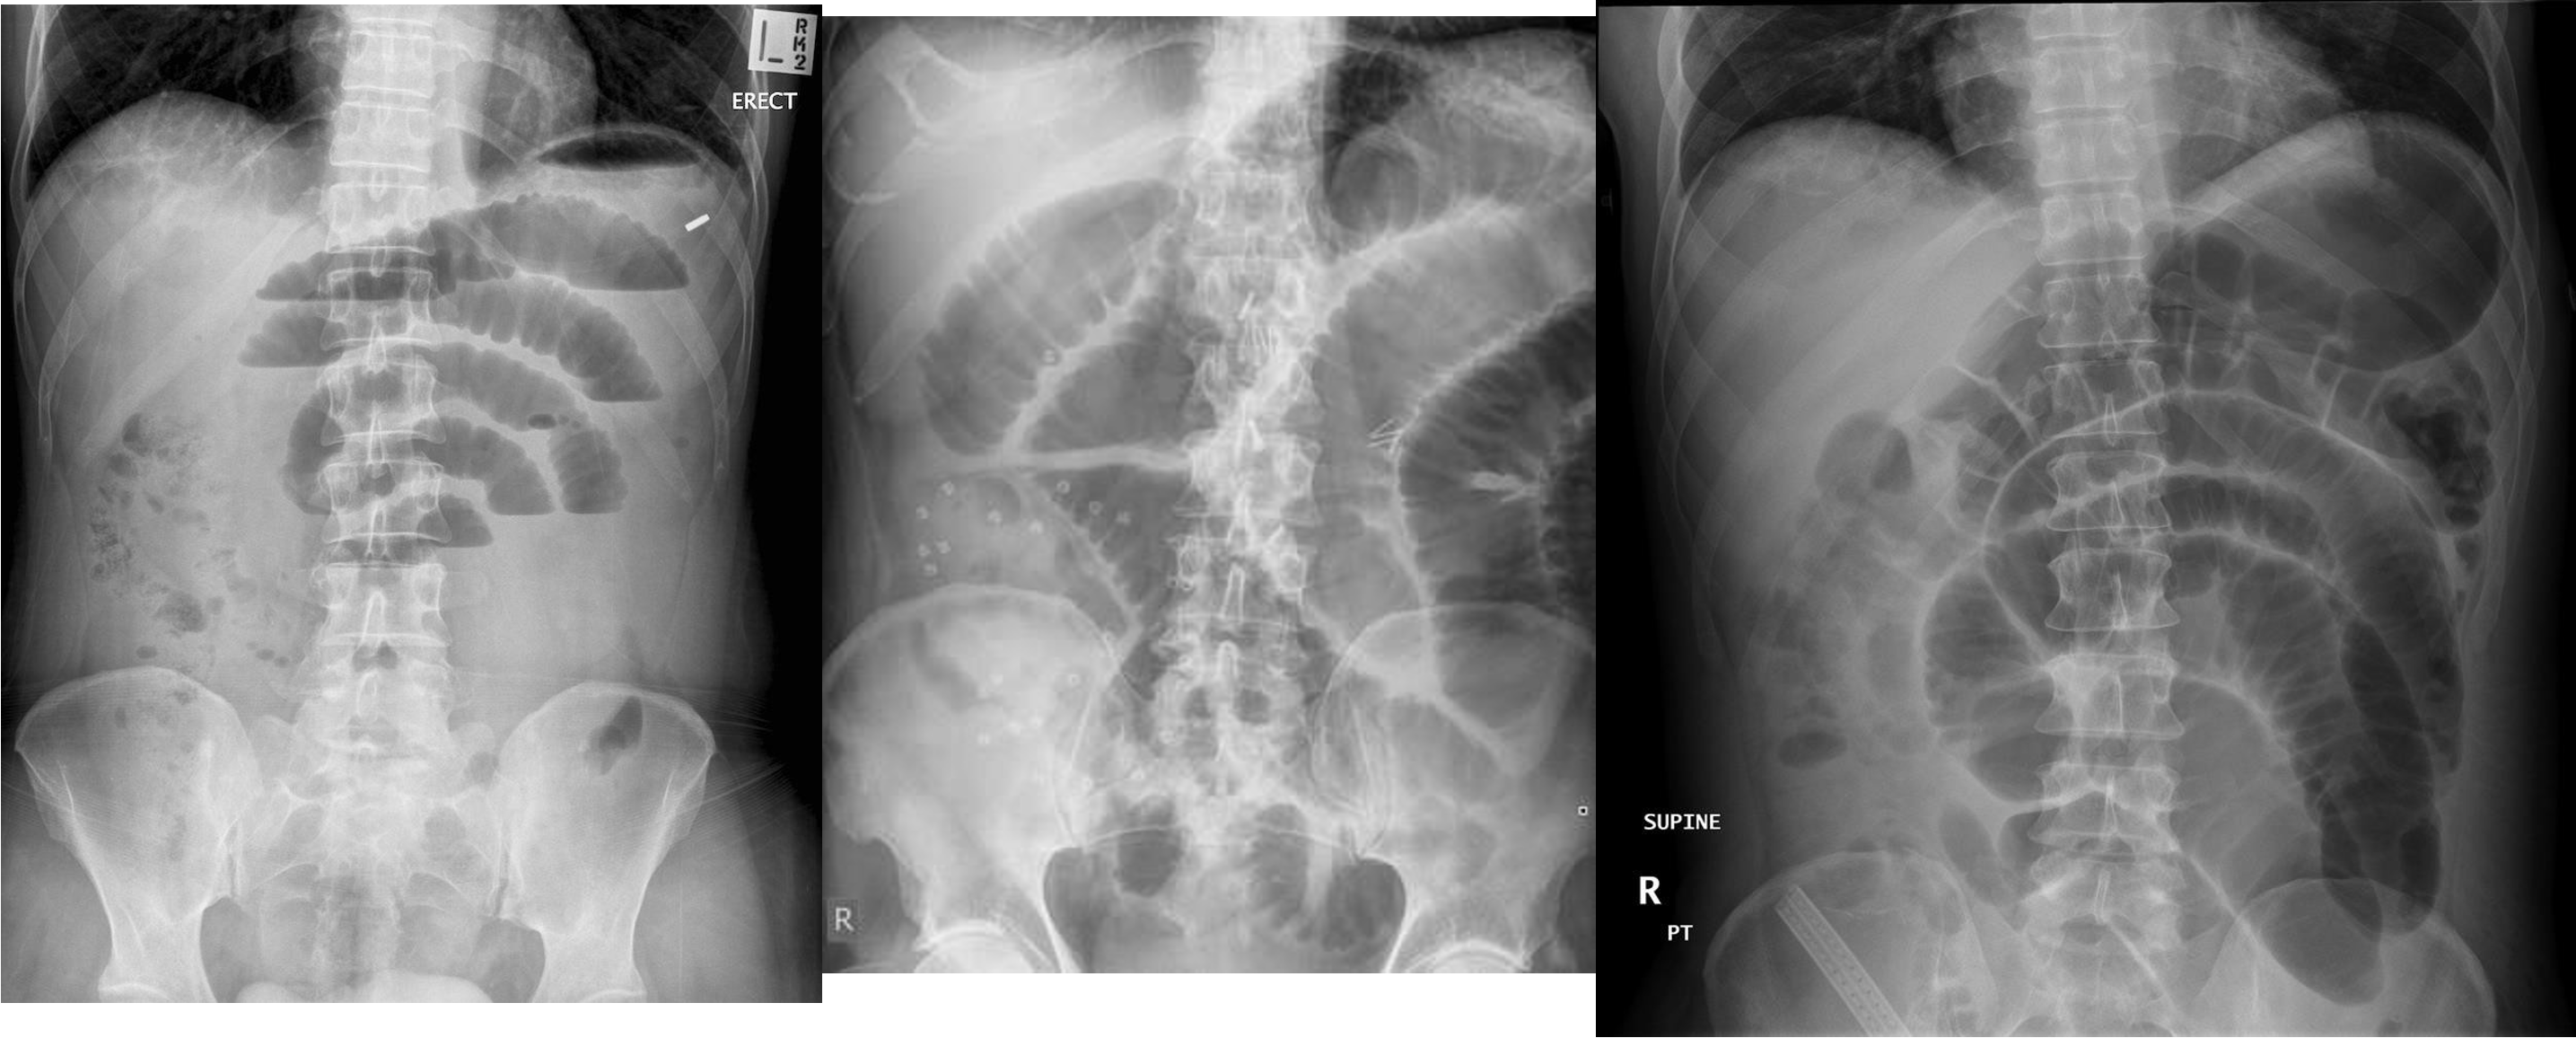

Abdomen Imaging

normal abdominal x-ray - normal gas pattern - lower pole kidney - gastric bubble is found - comment on bone

Free air under diaphragm - most commonly due duodenal perforation - (diff; perforated viscus, peptic ulcer, duodenal, penetrating truama, post surgical 8 days likely to disappear)

- free air

- erect - air fluid levels - should be not more than three - >5 significant 11 found -

- no free air under diaphgram - 8 fluid level, (evidence of bowel obstruction) (adhesion, hernia, IBD; Crohn, cancer, inturcucception, gallstones)

9 air fluids in large bowel - mucosal folds are not completed - highly suggestive of bowel obstruction

- dilated large bowel - mucosal folds are not complete - (diff; cancer, divertuclitis, volvolus, toxic megacolon?)

- if both small and large most likely nonmechanical paralytical illeus

2) Dilated bowel (diff; cancer colon) -

closed loop obstruction from both sides result large bowel most dangerous left side most common cancers

- coffe bean - omega sign - volvulus twisting around its axis - it is closed loop obstruction very dangerous - (treat clonoscopy decompression)

- volvulus

- abdominal x-ray - Dilated colon (diff - cancer colon, ulcerative colittis)

- 8 air fluid - small intestinal central - intistinal obstruction due adhesion - stack of coins. ++ NG tube aspiration relieve from vomitting

- dilated small bowel obstruction - stack of coins

- small bowel

2) large bowel - mucosal issnt complete periphery